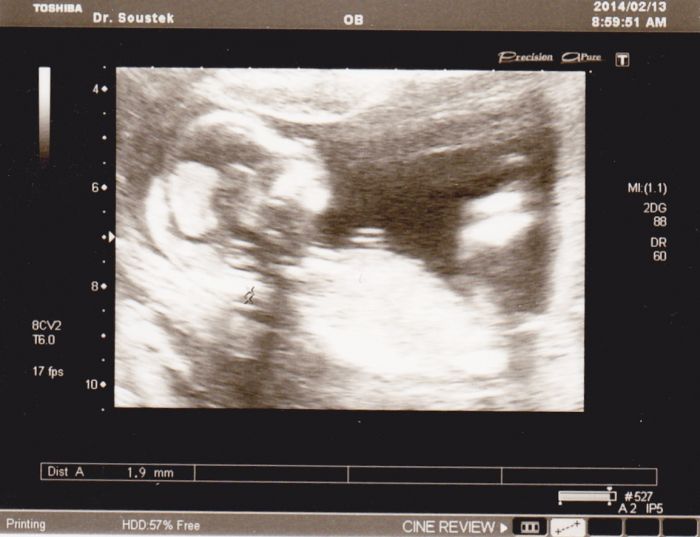

ahojte holky...představuji vám našeho prďolku...:-*.

Krásná fotka Pavli :-)